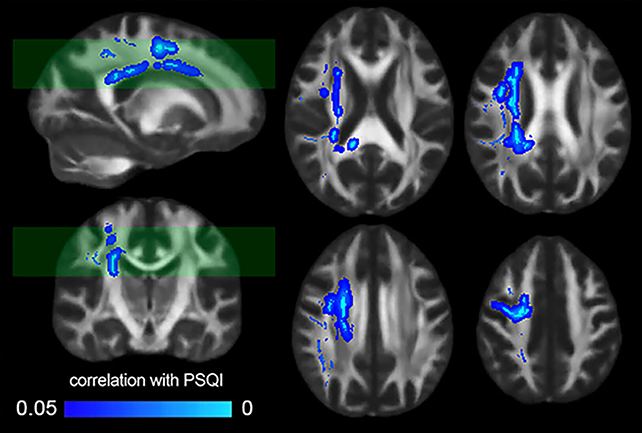

У межах роботи науковці проаналізували МРТ-скани 185 здорових добровольців і зіставили структуру «білої речовини мозку» з показниками Піттсбурзького індексу якості сну (PSQI). Результати підтвердили попередні дані: гірша якість сну асоціюється зі зниженням цілісності білої речовини.